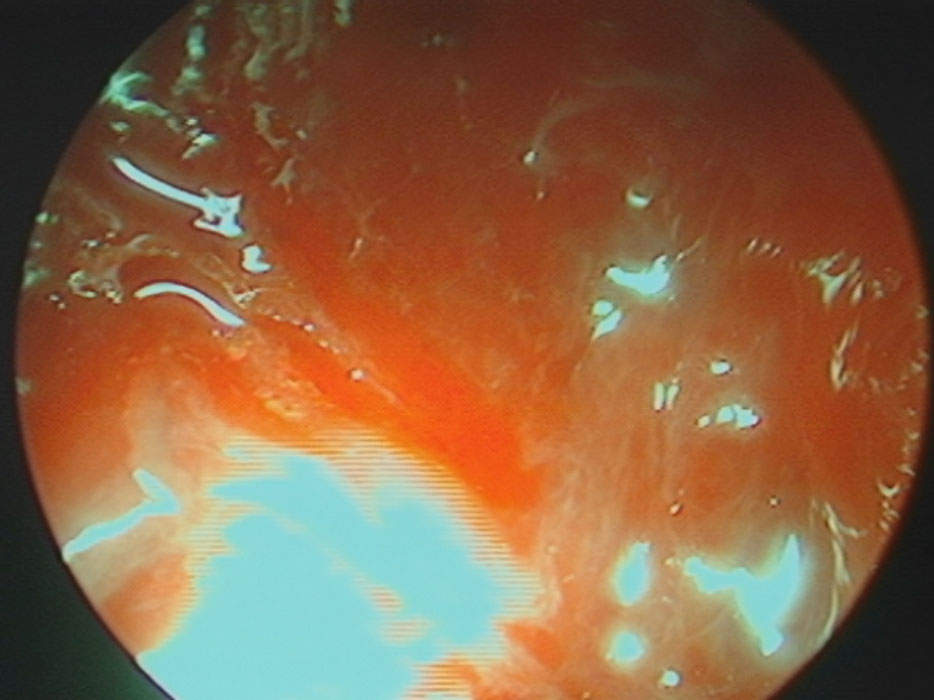

No.’24_69 手術前1

No.’24_69 摘出 前

No.’24_69  摘出 中

No.’24_69 摘出 後